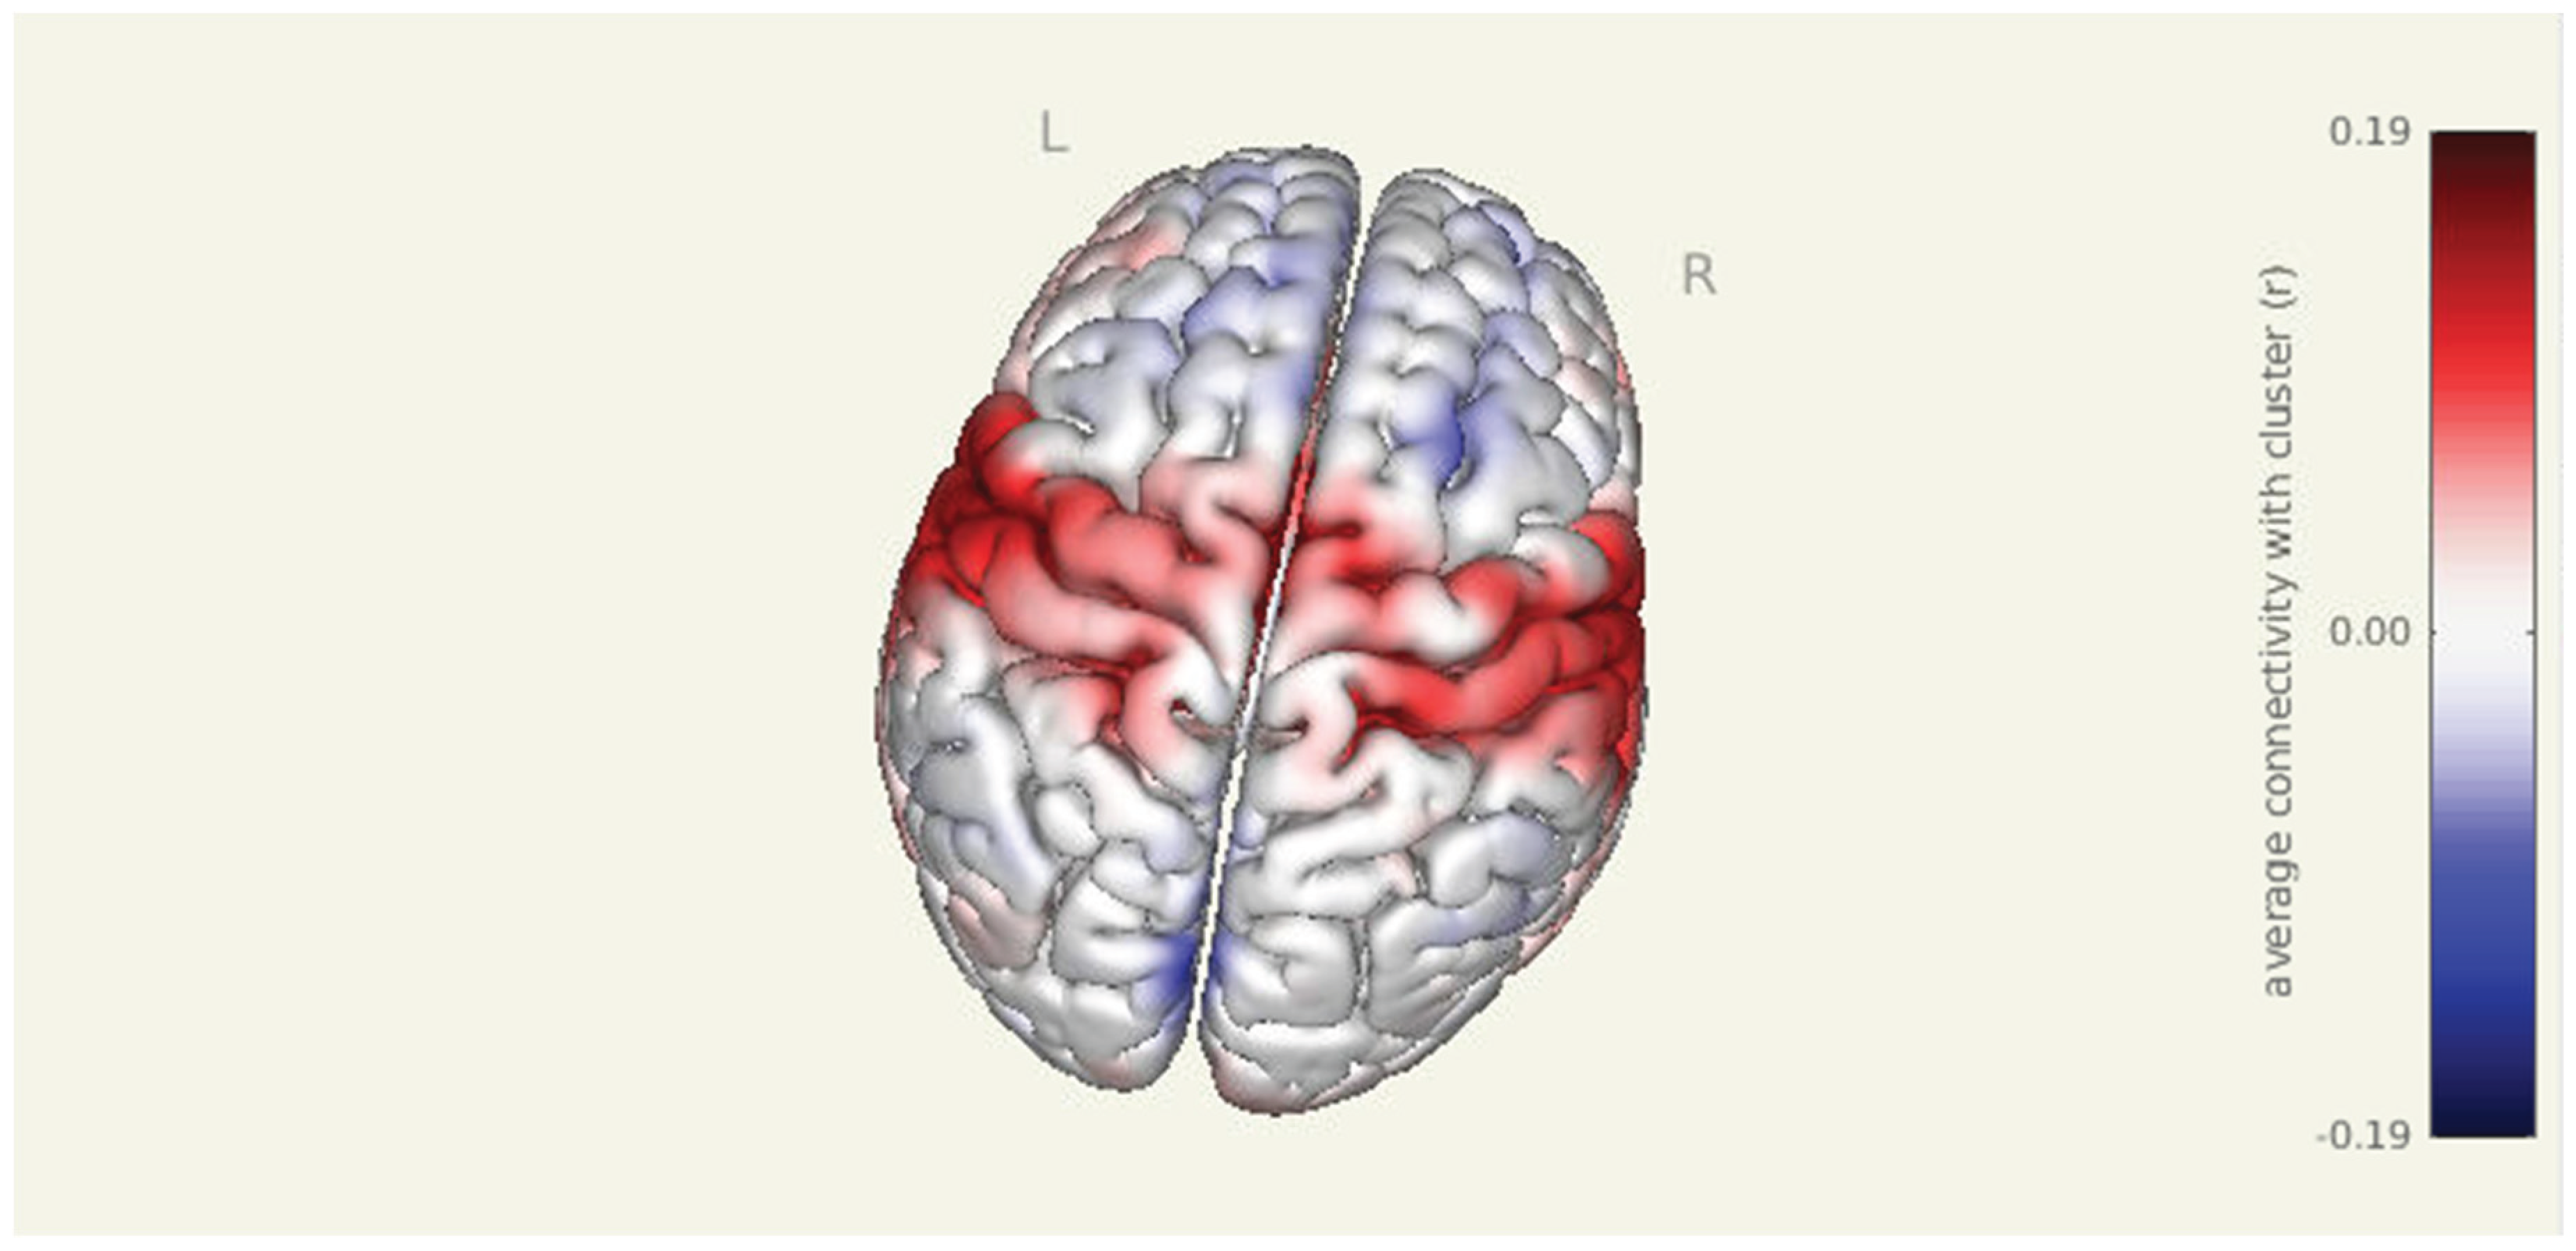

Prior to intervention, seed-to-voxel analysis from the amygdala revealed widespread connectivity with multiple cortical and subcortical regions. Significant clusters were observed in bilateral sensorimotor and frontal areas, including the left parahippocampal gyrus (MNI: -36, +06, -28; cluster size = 1396 voxels; p-FDR < 0.001), right superior parietal lobule (+38, -56, +60; 575 voxels; p-FDR < 0.001), right insular cortex (+46, -06, +16; 406 voxels; p-FDR < 0.001), and right thalamus (+18, +10, -16; 383 voxels; p-FDR < 0.001). Additional clusters were detected in the left superior parietal lobule, right cerebellum, and prefrontal cortex, further supporting elevated amygdala connectivity within regions implicated in sensory integration, emotional processing, and motor readiness.

Pre Amygdala Seed

Figure 1. Pre-intervention amygdala connectivity map. A 3D surface rendering illustrates widespread resting-state functional connectivity from the amygdala seed at baseline. Significant clusters were observed in bilateral cortical and subcortical regions, including the left parahippocampal gyrus, right superior parietal lobule, right insular cortex, and right thalamus (all p-FDR < 0.001).